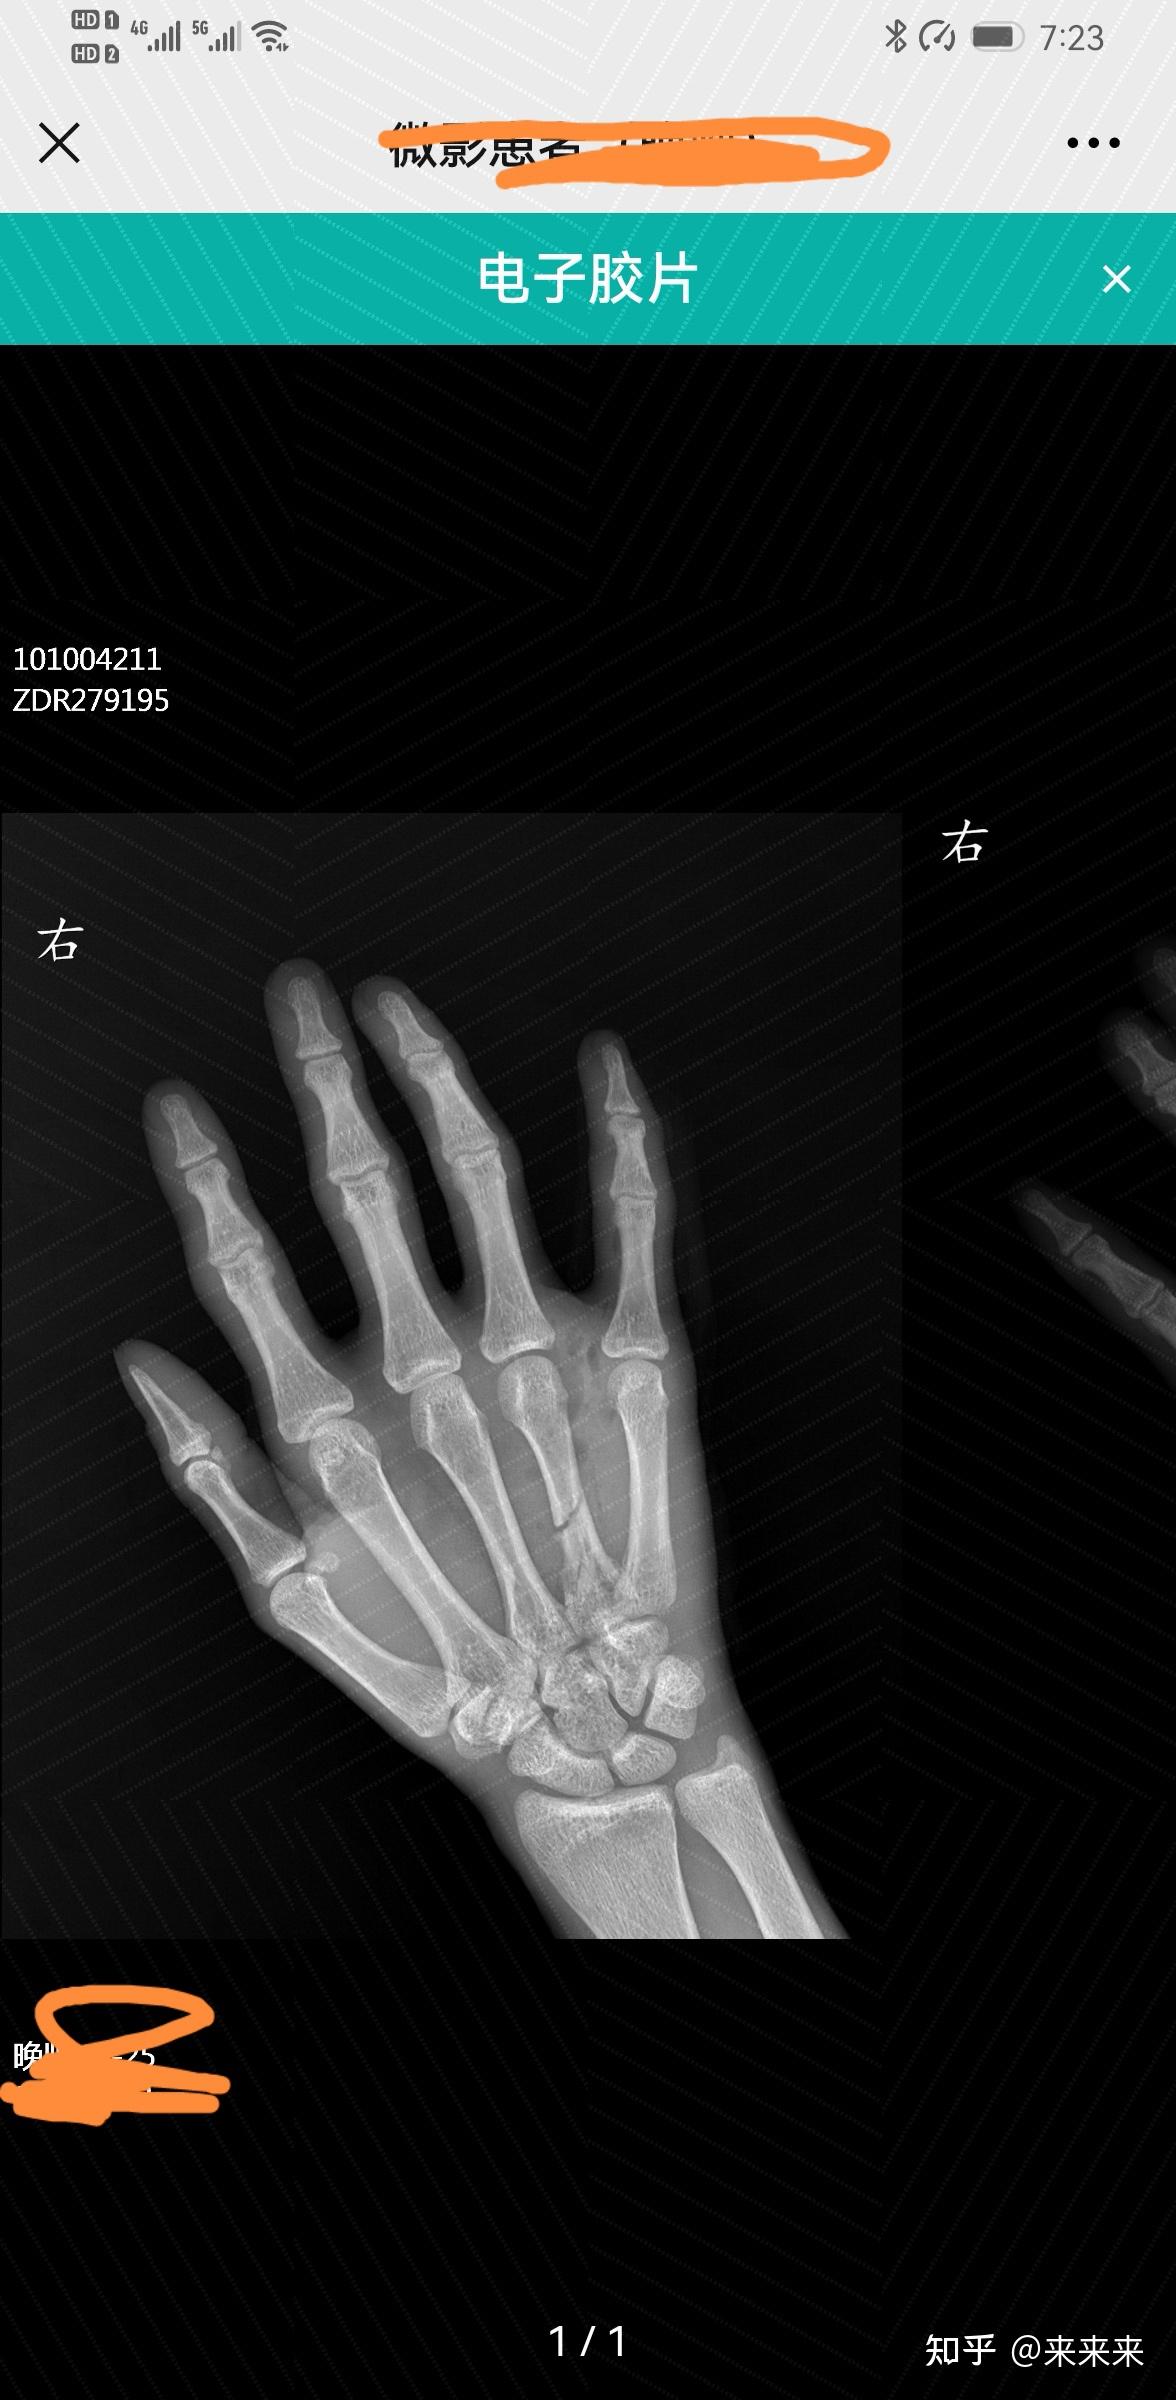

右手第四掌骨骨折保守治疗的第16天,恢复的是否不太理想? - 知乎

右手第四掌骨骨折